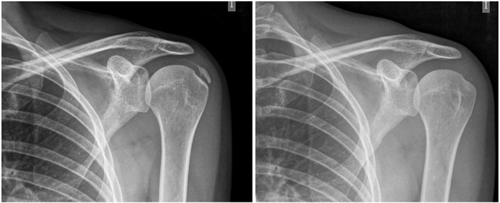

Fig. 5. A 44-year-old female patient, with calcific tendinitis of the left supraspinatus, of the resorptive type, who after 20 sessions of iontophoresis decreased pain measured by VAS from 10/10 to 4/10, and calcification from 22 mm to 0 mm (complete disappearance).